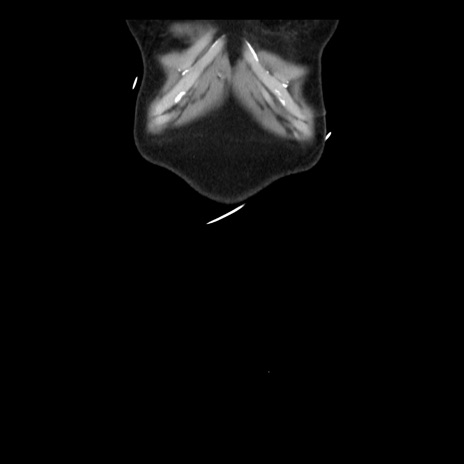

横断像